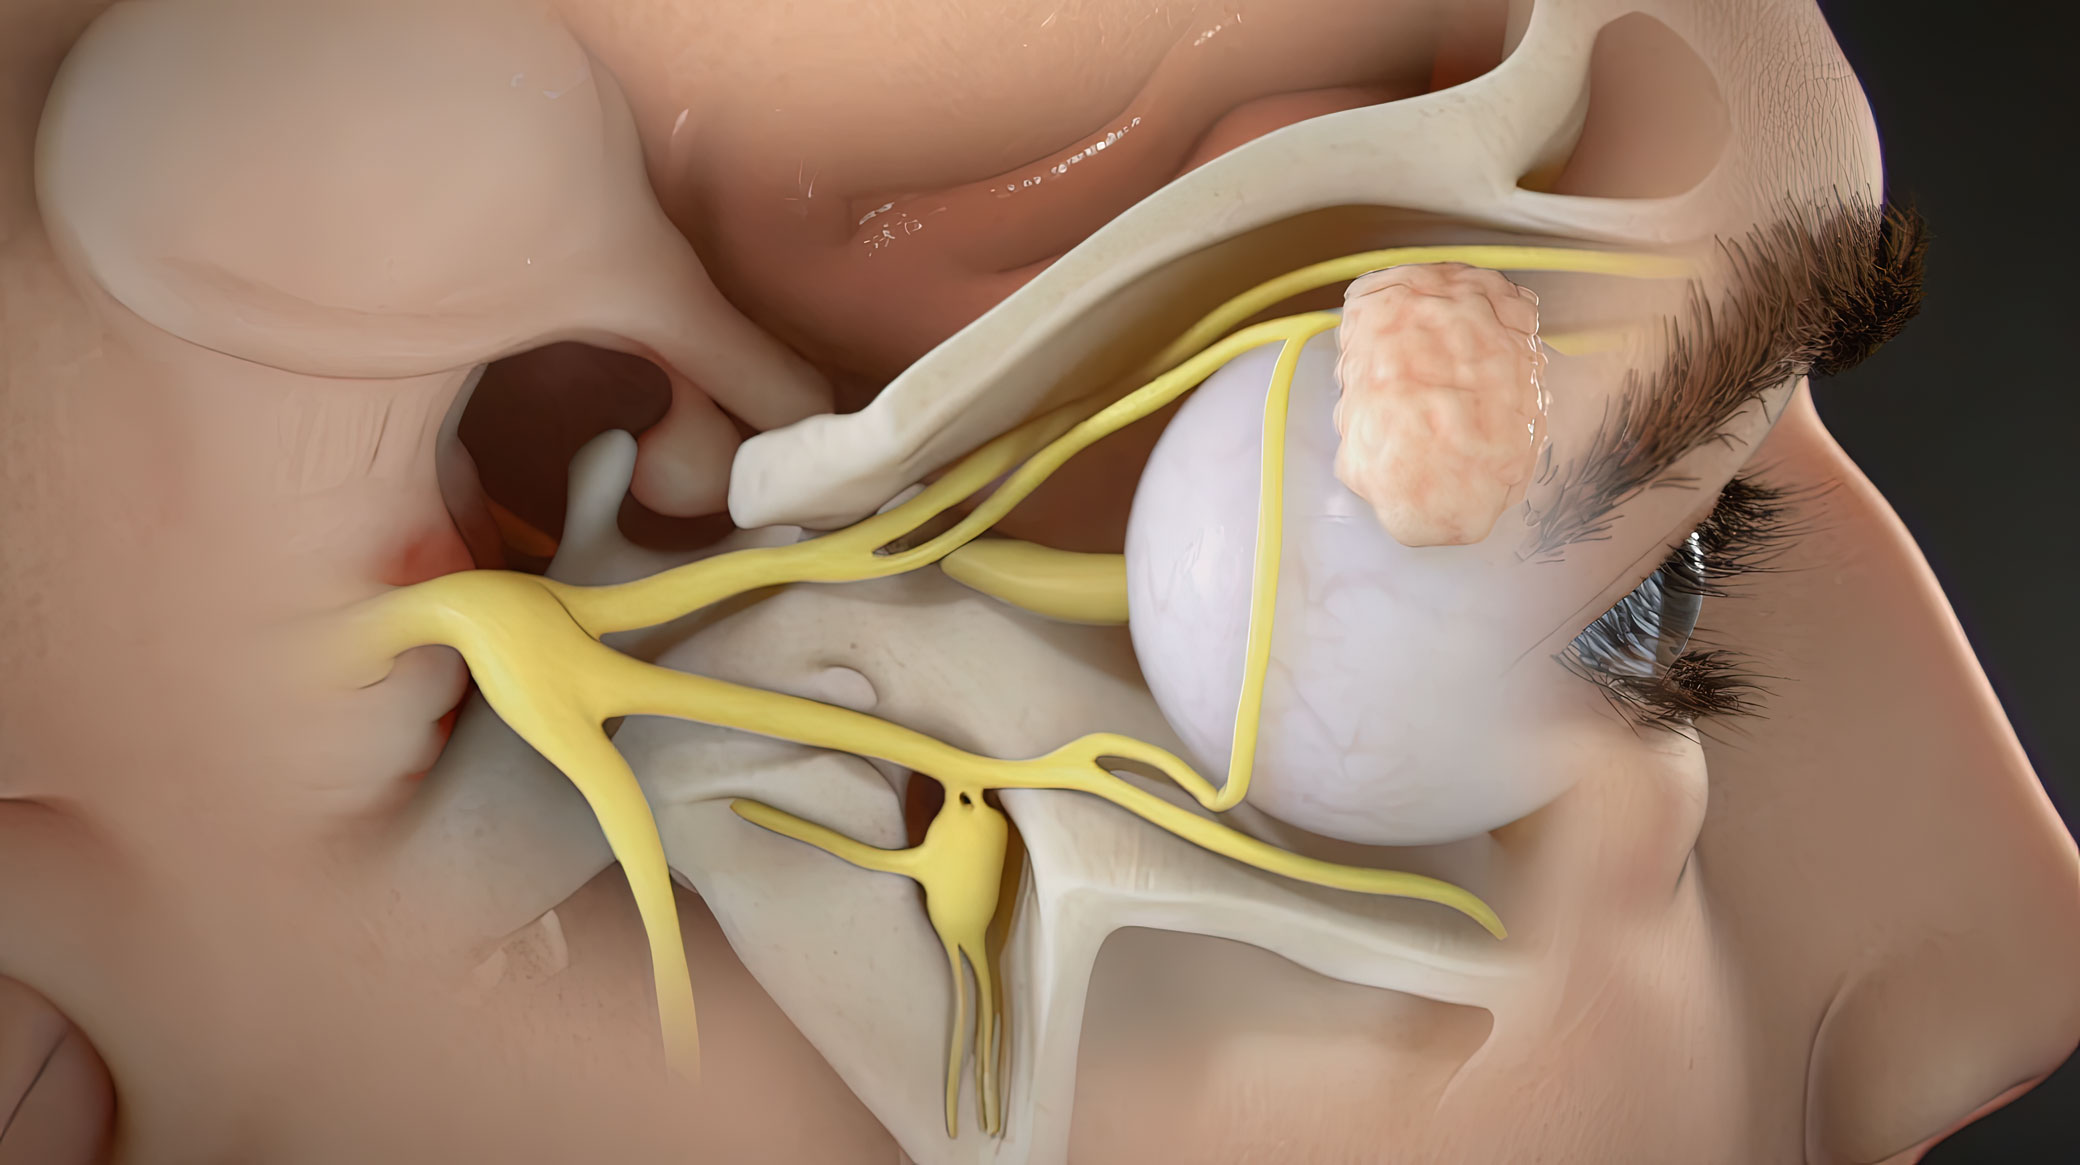

The world of medicine and healthcare is filled with complex concepts, intricate procedures, and marvels of human anatomy. Translating these intricate details into accessible and engaging visuals is no easy task. Ghost Medical Animation's team of animators and medical artists excel at merging the worlds of art and science, distilling complex medical information into eye-catching and informative illustrations.

With their keen eye for detail, the artists transform medical data, research findings, and clinical knowledge into visually appealing content. Each image and frame in their gallery serves as a bridge between the scientific realm and the general public, helping people comprehend medical concepts with ease while leaving them awe-inspired by the beauty of the human body's inner workings.

One of the most striking aspects of Ghost Medical Animation's Image Gallery is the diversity of subjects and medical fields covered. Whether it's depicting the intricacies of cellular biology, illustrating the intricacies of surgical techniques, or presenting the mechanism of action of pharmaceuticals, their artists are adept at handling a wide range of medical topics.

The team's expertise isn't limited to still medical illustrations; they are also masters of animation. They bring medical concepts to life through fluid and captivating animations, making it easier for both professionals and laypeople to understand complex medical processes. Through their skillful use of motion, the animations breathe life into scientific ideas, helping viewers envision dynamic physiological processes and medical advancements.